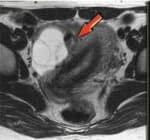

Los quistes simples de hasta 30 mm de tamaño que se presentan en mujeres en edad fértil son normales y no peligrosos. Si el tamaño de la formación después de la menopausia es de hasta 70 mm, lo más probable es que sea benigno. Las inclusiones extrañas con un diámetro de 70 mm o más son difíciles de analizar en ultrasonido, por lo que se realiza una resonancia magnética.

neoplasia folicular

Formaciones funcionales en ecografía: folicular y lútea